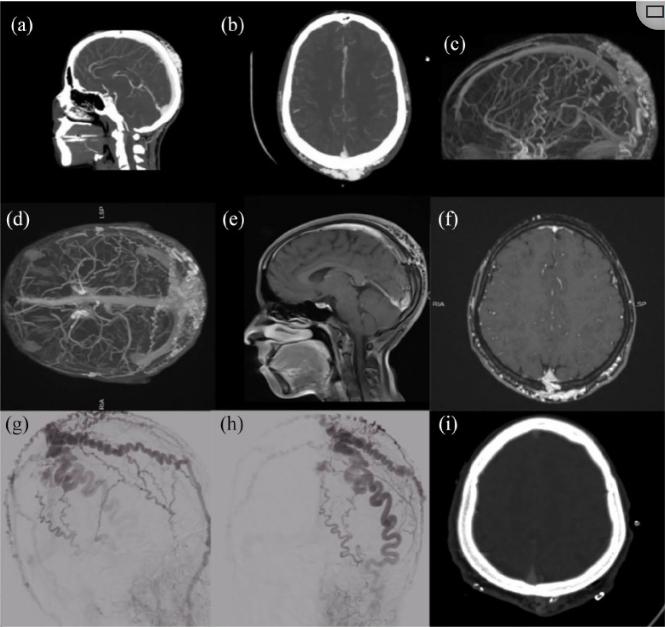

图二、患者顶枕AVM的术前影像和术后结果。对患者进行的脑CT血管造影术的轴向(a)和矢状(b)切面显示AVM,病灶位于枕部头皮,尺寸约为3cm×2cm。病灶通过两侧扩大的浅颞动脉和枕动脉供血,没有颅骨受累的证据。具有矢状(c)和轴向(d)视图的大脑重建MRA图像更好地显示了AVM。病灶呈厚网状排列,位于头皮后部,由两侧扩大的弯曲STAs和枕动脉分支供血。静脉对比矢状面(e)的T1W图像显示病灶血流至上矢状窦的后部,这一点在图(f)中选择的轴向切面上也很明显。没有证据表明AVM向颅内延伸。DSA显示左侧颈外动脉注射前后投影,显示左侧STA无颅内受累。与左侧相比,右侧颈外动脉注射的横向投影显示了类似的结果(g,h)。(i)AVM术后头部CT扫描